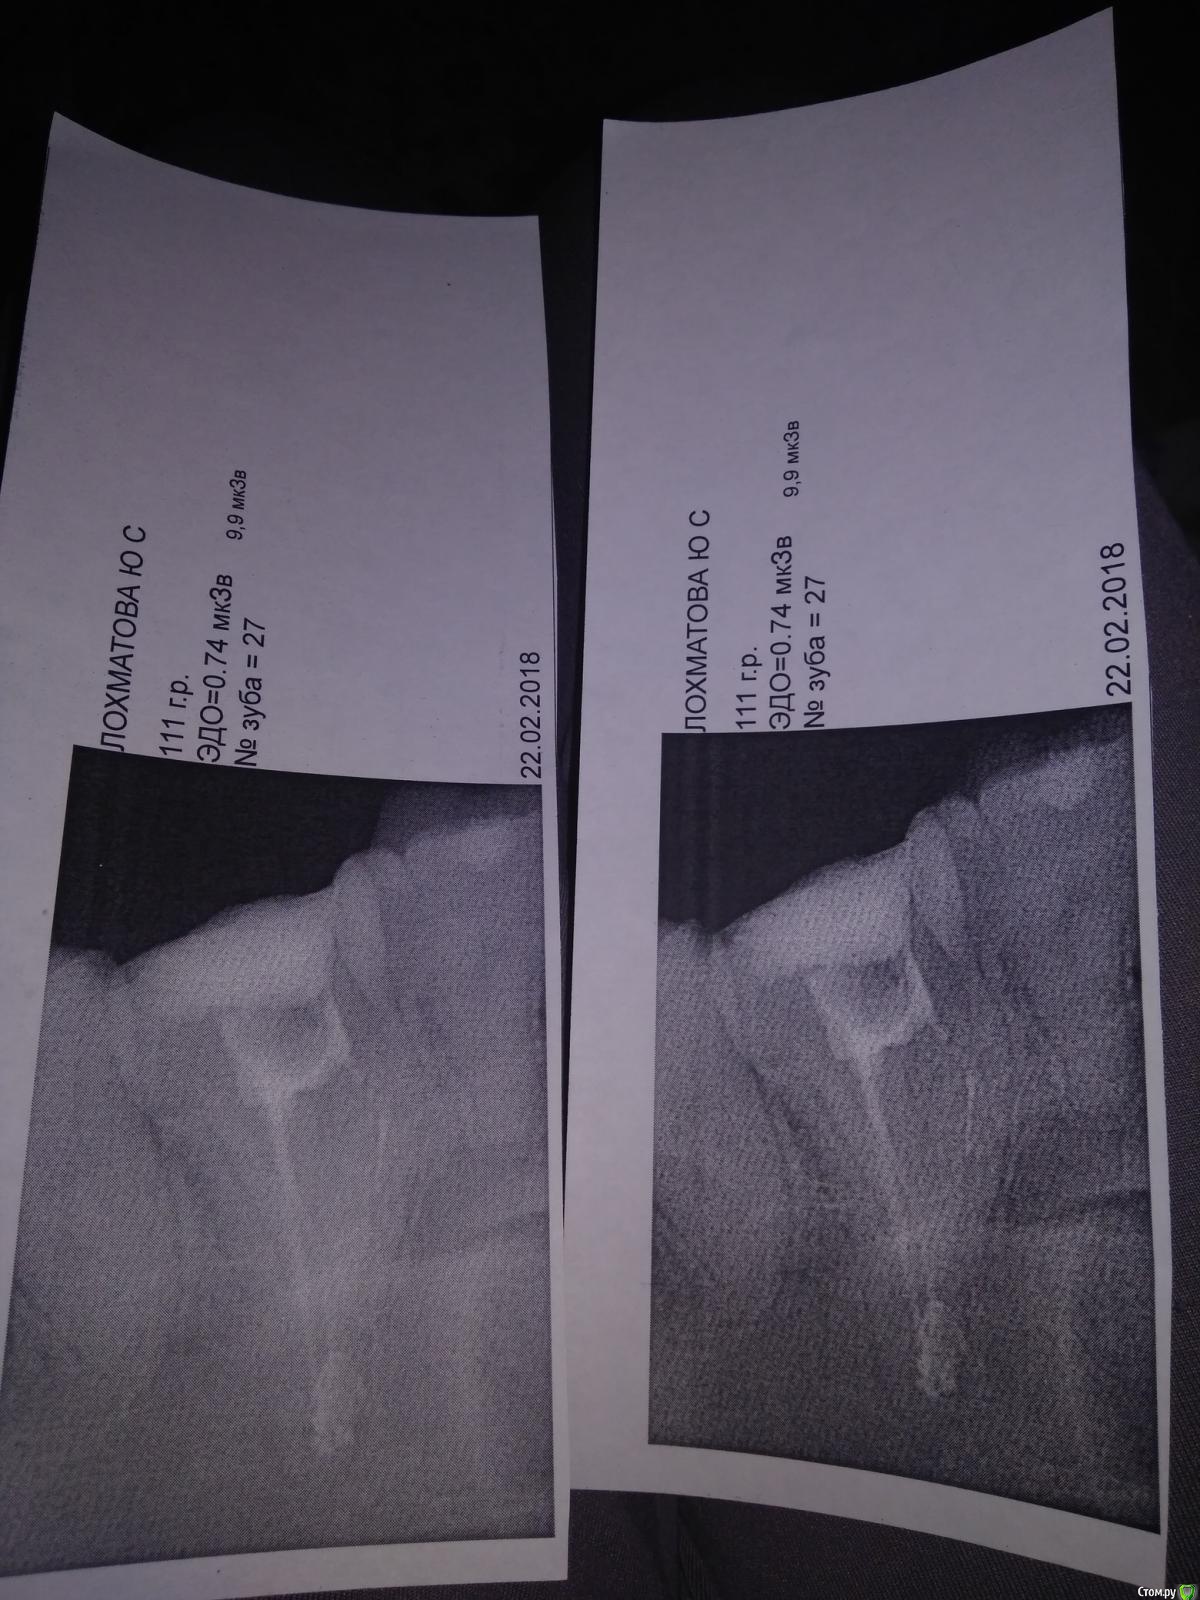

Yukchka Опубликовано 22 февраля, 2018 Поделиться Опубликовано 22 февраля, 2018 Доброго вечера, очень прошу помощи! Изначально врач пролечил глубокий кариес 27 зуба слева сверху(зуб беспокоил раз в пол года сильными болями), поставил постоянную пломбу без удаления нерва.После зуб начал болеть без раздражителей(на холодное горячее не реагировал) , сделали снимок , оказался пульпит, вскрыла зуб , прочистила и поставила какую то пасту убивающую нерв. Через 5 дней прочистила каналы, все эти 5 дней ныл зуб, боли после еды, ночью не болит, как просыпаюсь начинаю разговаривать начинает ныть, интенсивность боли разнаЯ, после еды очень сильно болит.На холодное горячее не реагирует, на постукивание тоже. После чистки каналов на следующий день почувствовала облегчение, зуб не беспокоил, но вечером началось... Вся челюсть начала ныть без раздражителя. На следующий день сделала рентген, снимок прилагаю. 1 фото снимок сделан до чистки каналов, второй сегодня. Зуб по прежнему ноет, что делать мой врач не знает, разводит руками((( Ссылка на комментарий

Yukchka Опубликовано 22 февраля, 2018 Автор Поделиться Опубликовано 22 февраля, 2018 Снимки Ссылка на комментарий